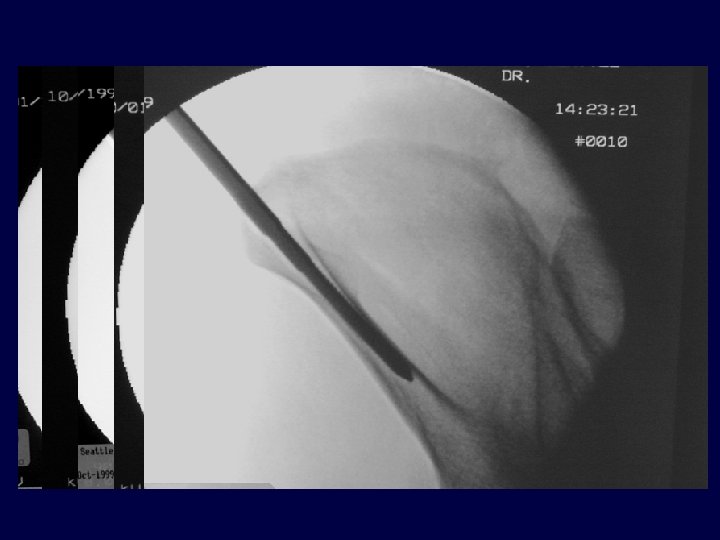

Technical Details: AIIS frames… • Fluoro dependent: • • • 1. 30/30 outlet/obturator oblique (confirm entry location and direction) 2. Iliac oblique (confirm direction above sciatic notch) 3. Inlet/obturator oblique (confirm depth) • Incisions directed toward the anticipated final location • Blunt dissection • Aim: fluoro According to Consider partial closed reduction first!

• Outlet Obturator Oblique Image